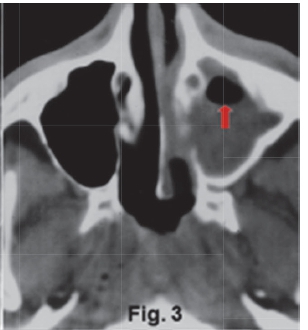

The intra-oral radiograph (Fig.1) shows a lesion at the apex of the 18. The lesion has extended to destroy a portion of the antral floor. There is also loss of the lamina dura and the presence of a "halo" (green arrow) of periosteal new bone suggestive of an osteitis. Some authors refer to this lesion as a localized mucositis or sinusitis of the left maxillary sinus. A Water's view of another patient (Fig. 2) shows an opaque right maxillary sinus and a classic air-fluid level (red arrow) in the left sinus, features which are consistent with acute sinusitis. Another example of acute sinusitis is discernible on the axial CT (Fig. 3) scan of another patient showing a clearly opacified left maxillary sinus with mucosal thickening and an air-fluid level (red arrow). Acute sinusitis presents clinically with facial pain, headaches, local tenderness and purulent discharge and is a common infection of the maxillary sinuses. Figure 4 is a Water's view of the maxillary sinuses showing a very sclerotic right sinus and small sclerotic maxillary antra in the left sinus (purple arrows), which is suggestive of chronic sinusitis. An axial CT scan (Fig. 5) of the same patient shows marked thickening of the walls of the right maxillary sinus with a thickened mucosa. The medial wall defects indicate that prior nasal antrostomies had been performed (blue arrow).